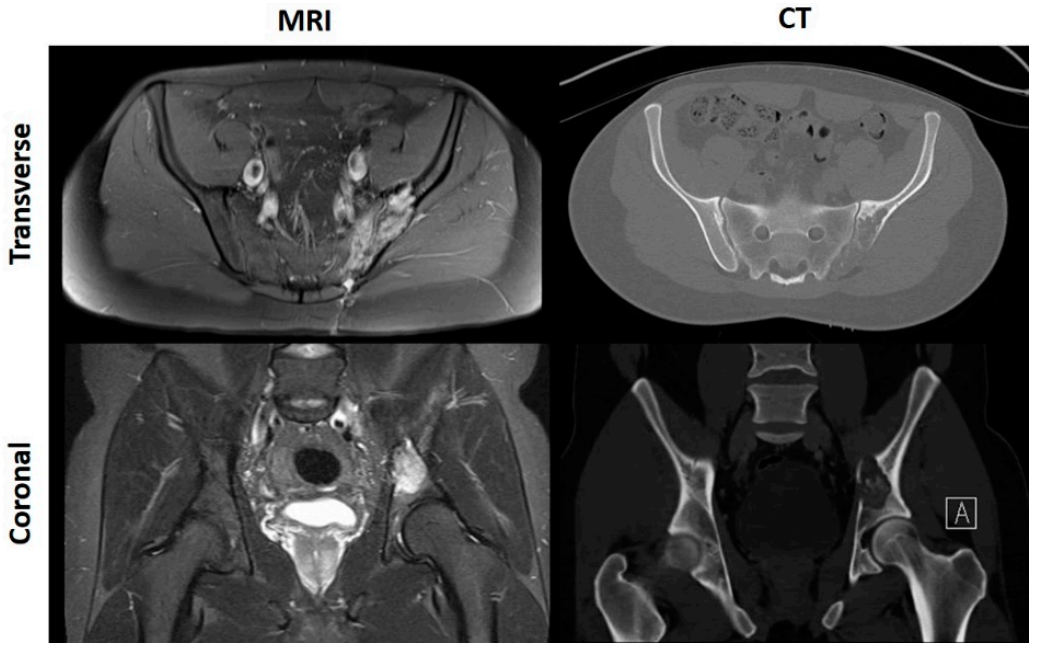

2. Pre-Operative Imaging

2.1. Current Guidelines

2.2. Magnetic Resonance Imaging and Positron Emission Tomography (MRI/PET) Approach